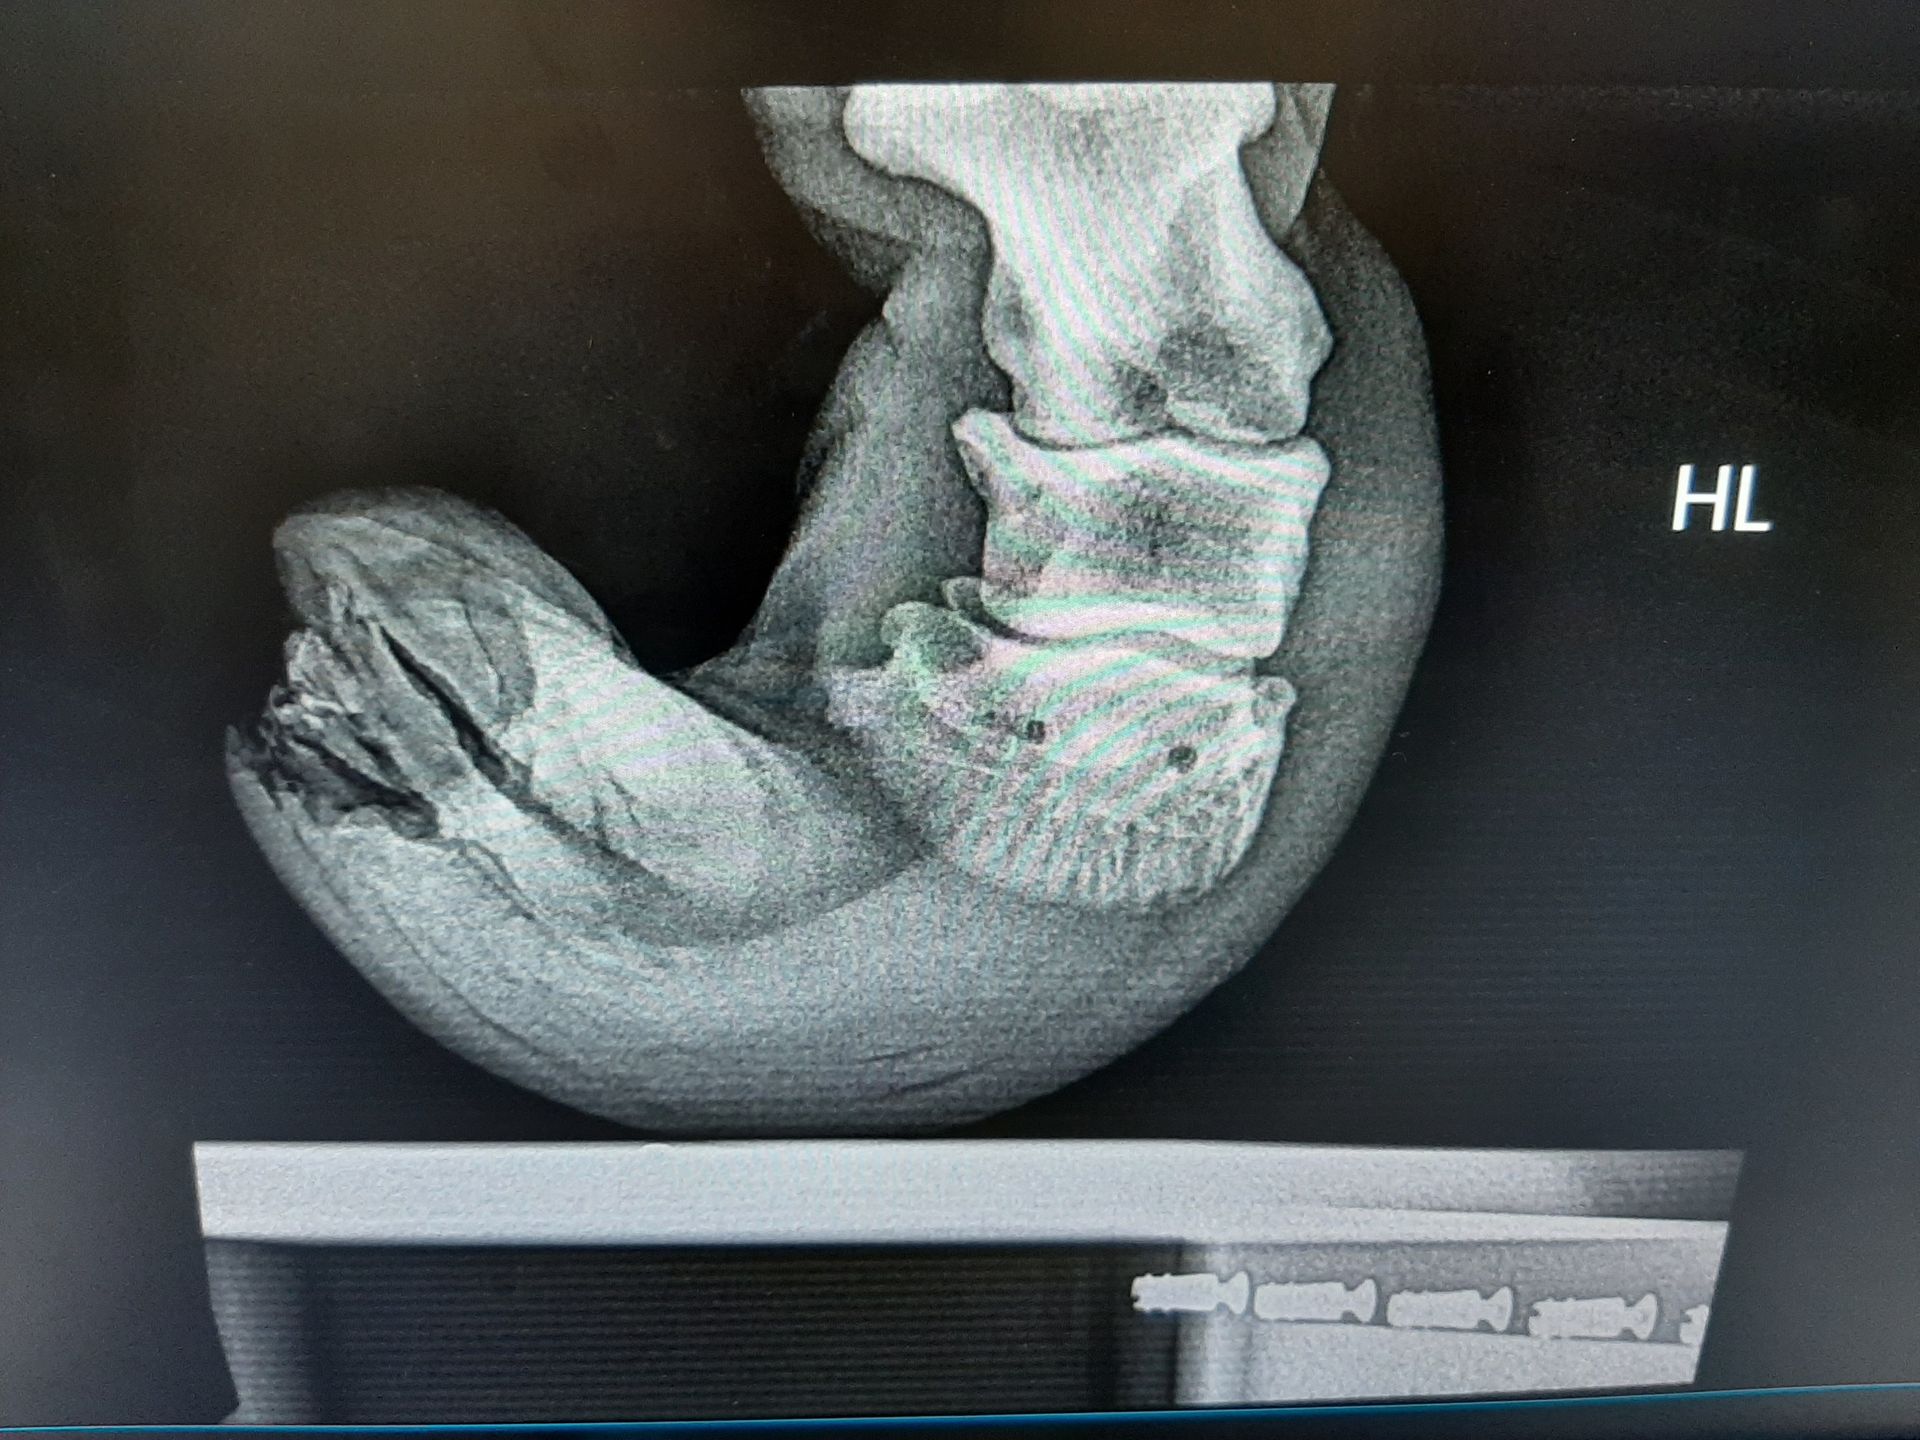

Fallbeispiel

Shetlandpony mit vernachlässigten Hufen

Behandlung: Entfernen des übermäßig gewachsenen Hufhorns

WaS war der Fall

Dieses Shetty wurde vorgestellt mit viel zu langen Hufen. Nach einer Kontrolle der Gelenken mittels Röntgenbildern wurde das überschüssige Horn entfernt.

Auf den Bildern sieht man, wie lang die Hufe sind. Nach dem Ausschneiden (Bilder fehlen leider) stand das Tier schon viel besser.